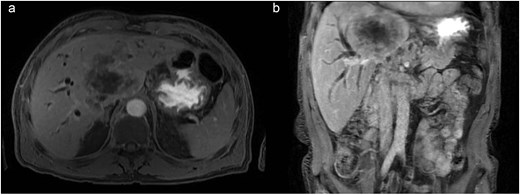

During admission, the blood tests reported abnormal liver enzyme levels: total bilirubin of 17.9 mg/dl, direct bilirubin of 13.9 mg/dl, aspartate aminotransferase (AST) of 108 U/L, alanine transaminase (ALT) of 118 U/L, gamma-glutamyl transferase of 1347 IU/L, and alkaline phosphatase of 588 IU/L. The blood tests also reported abnormal coagulation levels: INR of 2.04, activated partial thromboplastin time of 41.5 s. An abdominal CT scan revealed a central infiltrative lesion in the hepatic parenchyma, affecting segments I, IV, and VIII, measuring ~11.0 × 8.8 cm (Fig. 1a). There was an obstruction of the bile duct at the confluence of the hepatic ducts and involvement of segmental ducts of both lobes with dilation of the intrahepatic bile ducts (Fig. 1b). The lesion was in contact with the middle hepatic vein, the distal segment of the portal vein trunk, the right and left portal branches, and the retro hepatic inferior vena cava. Thus, the diagnosis of neoplasia was suspected, and both hepatocellular carcinoma and cholangiocarcinoma were considered.

(a) Axial contrast enhanced CT scan shows a central infiltrative lesion in the hepatic parenchyma, affecting segments I, IV, and VIII, measuring 11.0 × 8.8 cm. (b) Coronal contrast enhanced CT scan the mass causing obstruction of the bile duct at the confluence of the hepatic ducts and involvement of segmental ducts of both lobes.